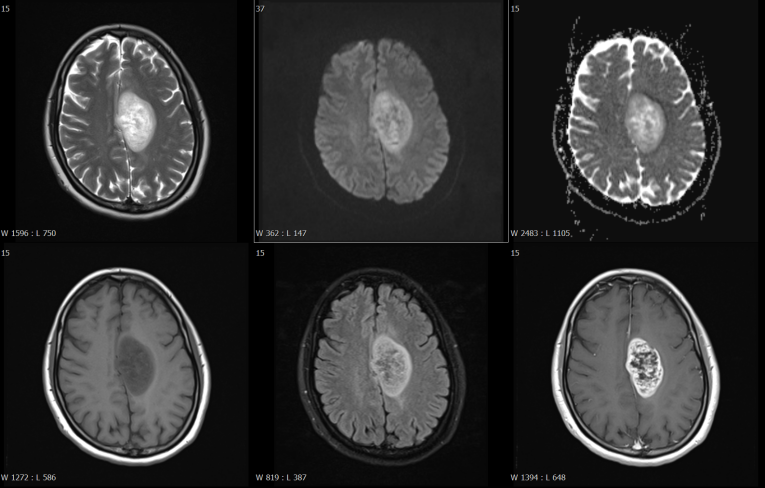

磁共振檢查方面,開展了高技術(shù)的增強(qiáng)掃描動態(tài)分析,動態(tài)灌注掃描、波譜分析,為腫瘤鑒別提供了有效方法,比如腦內(nèi)膠質(zhì)瘤、淋巴瘤的鑒別。

富血供病變---高級別膠質(zhì)瘤